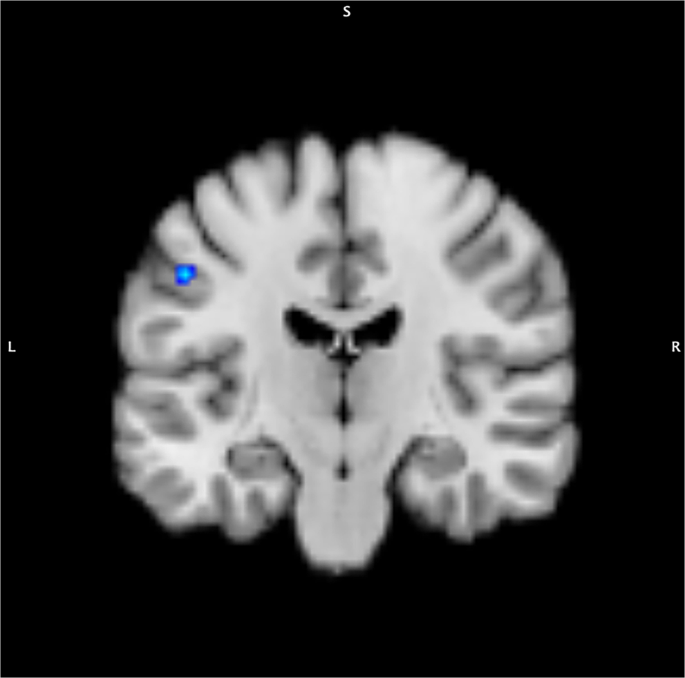

Cerebral blood flow

In hypothyroidism, a significant decrease in CBF was observed in 1 cluster of left postcentral gyrus (cluster size 368 mm3, x −53; y −15; z 41, maximum ALE value of 0.0087) (Fig. 3 & Table 3).